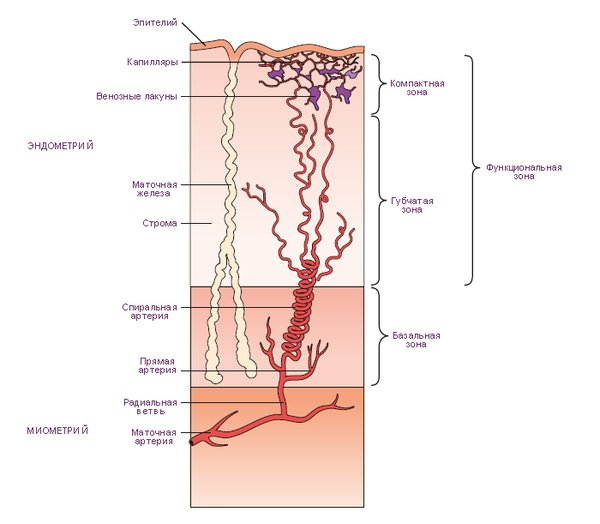

Линейный эндометрий – термин, который часто встречается в заключениях ультразвуковых исследований. Что же он обозначает? Эндометрий состоит из трех слоев: базального (который не обновляется), функционального (обновляющегося ежемесячно) и эпителиального (покровного). В первой и частично во второй фазах менструального цикла все эти слои обладают схожими показателями проницаемости, плотности и эхогенности. При этом границы между слоями имеют значительно более высокую эхогенность, что позволяет визуализировать их на исследовании в виде четких прямых линий, что и дало повод для использования данного термина.

Таким образом, наличие линейного эндометрия на первой и частично на второй фазе цикла считается нормальным и является важным условием для успешного зачатия. Однако, если подобное состояние наблюдается на других этапах цикла, это может указывать на наличие патологии.

Если линейный эндометрий обнаружен на первой фазе или в начале и середине второй, это считается нормой. Такое состояние не только безопасно, но и необходимо для успешного зачатия и вынашивания ребенка. Оно также косвенно указывает на адекватный уровень эстрогена в организме, поскольку регенерация эндометрия происходит своевременно и активно.

Исчезновение линейной структуры в конце второй фазы свидетельствует о том, что на организм начинает действовать прогестерон. Под его влиянием процессы разрастания становятся менее выраженными, и линейная форма постепенно исчезает. Это нормальное явление, и если изменения в менструальном цикле происходят именно так, то не стоит предпринимать никаких действий, увидев такую формулировку в результатах УЗИ.